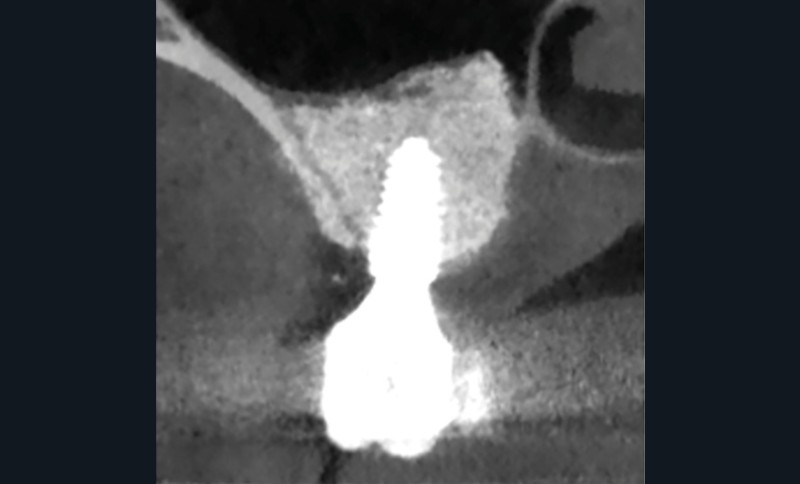

Quatre mois après la suppuration initiale, une fistule est apparue à l’apex de l’implant 16 (fig. 2a). Cette fois, l’examen CBCT a révélé une résorption osseuse considérable (fig. 2b à d). Une chirurgie exploratrice a donc été décidée.

Après une anesthésie locale, un lambeau muco-périosté (pleine épaisseur) vestibulaire a été soulevé. Aucun excès de ciment n’a été observé, seulement du tissu de granulation mélangé à des matériaux d’augmentation osseuse qui ont dû être retirés.